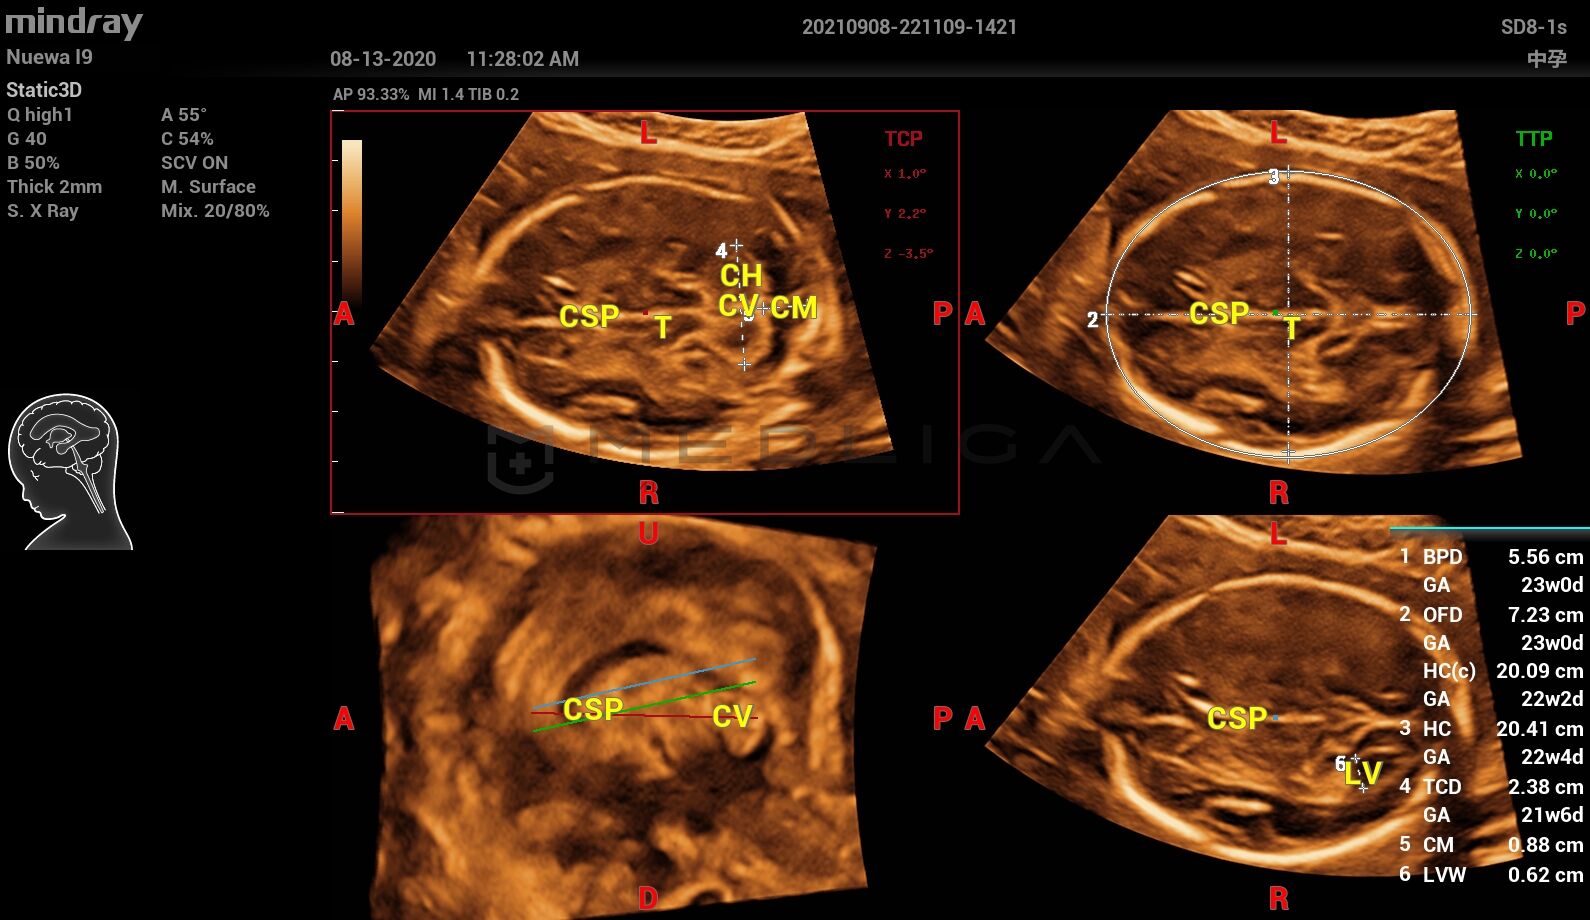

• Полностью автоматическое распознавание срезов, 4 стандартных среза ЦНС

• Высокоточные измерения, 6 часто используемых фотометрических параметра

При нажатии на трехмерное изображение мозга плода незамедлительно будут получены

стандартные сканируемые плоскости ЦНС:

• MSP — интеллектуальная медиальная сагиттальная плоскость

• TCP — трансцеребральная плоскость

• TTP — трансталамическая плоскость

• TVP — трансвентрикулярная плоскость

набор соответствующих анатомических измерений:

• BPD — обмер и вычисление бипариентального размера головы

• HC — окружность головы

• OFD — лобно-затылочный размер головы

• TCD — межполушарный размер мозжечка

• CM — ширина большой цистерны

• LVW — ширина боковых желудочков